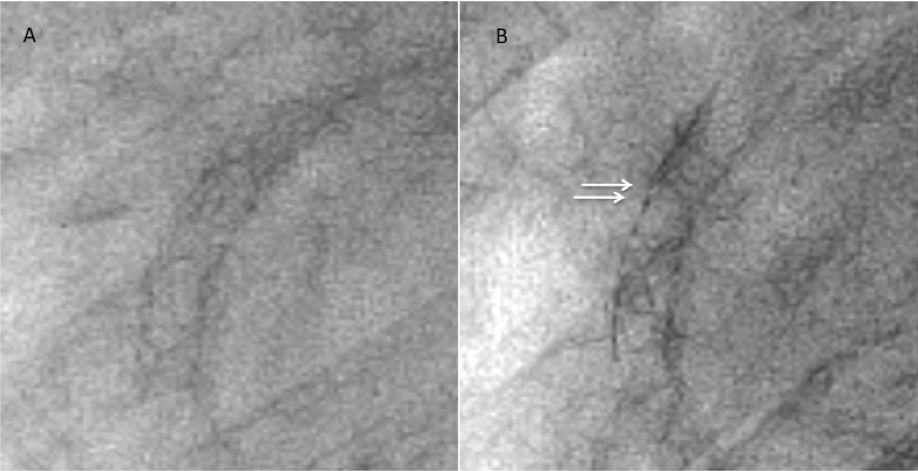

Figure 3. Comparison of fluoroscopic images (A) immediately after Nobori stent deployment and (B) 7 months later, showing 2 different points of stent fracture (click thumbnail to view larger image).

In addition, plain fluoroscopic images revealed 2 gaps in the stent strut, suggesting SF (Figure 3B), which was then confirmed by IVUS imaging (Figure 4). We diagnosed the case as ACS due to SF, and treated the site with adjunctive stenting. After predilatation with a 3.5 × 10 mm balloon, a 3.5 × 23 mm PROMUS stent (Boston Scientific) was deployed, followed by postdilation with an excellent result (Figure 2B).